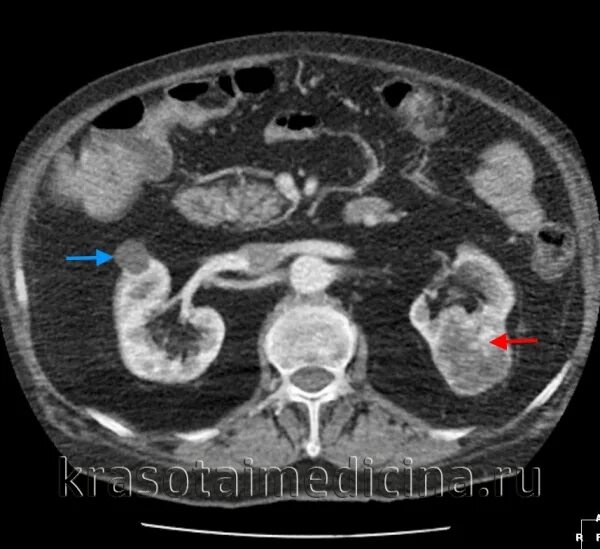

Код мкб кисты почек у взрослых